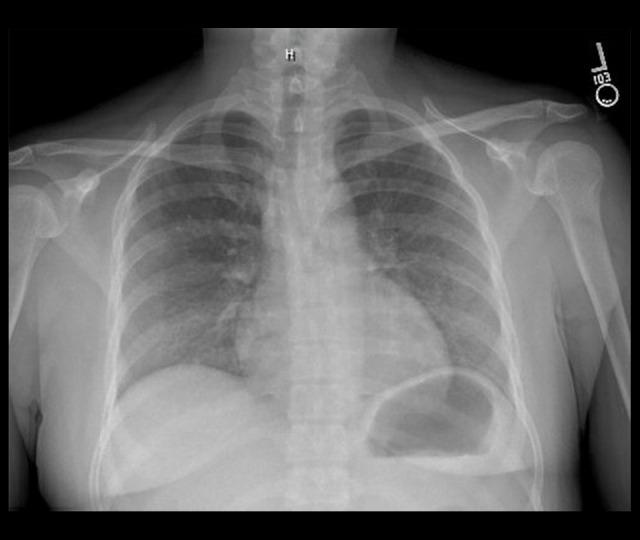

BACKGROUND Drug-induced anti-neutrophil cytoplasmic antibody (ANCA)-associated vasculitis (AAV) should be suspected in patients on certain medications who present with inflammatory ocular, constitutional, pulmonary, and/or renal manifestations. Here, we present a case of propylthiouracil (PTU)-induced AAV presenting initially with red eye, and review important diagnostic and management considerations for this uncommon disorder. CASE REPORT A 34-year-old woman with hyperthyroidism taking PTU presented with red eye, later followed by fevers and hemoptysis. She was found to have episcleritis, diffuse alveolar hemorrhage, and microhematuria. The infectious diseases workup was unrevealing. Laboratory evaluations were notable for a high-titer perinuclear ANCA and elevated anti-myeloperoxidase antibodies. Renal function was normal. She was ultimately diagnosed with PTU-induced AAV. PTU was promptly discontinued and she was treated with pulse-dose methylprednisolone for 3 days, followed by prednisone 60 mg daily. A kidney biopsy revealed pauci-immune focal segmental necrotizing and crescentic glomerulonephritis. Given an allergy to methimazole, she underwent thyroidectomy and was ultimately treated with rituximab. Her steroid doses are progressively being tapered and she has complete resolution of symptoms. CONCLUSIONS PTU-induced AAV is a rare and serious condition. Our patient presented with ocular symptoms prior to more commonly recognized pulmonary and renal manifestations. Patients may have favorable outcomes if PTU is discontinued promptly, but patients with vital-organ involvement may require treatment with steroids and may need additional immunosuppression.

一名 34 岁患有甲状腺功能亢进症的女性正在服用 PTU,出现眼红,随后出现发热和咯血。她被发现患有巩膜炎、弥漫性肺泡出血和镜下血尿。传染病检查无异常。实验室评估的特点是核周型 ANCA 滴度高和抗髓过氧化物酶抗体升高。肾功能正常。她最终被诊断为 PTU 诱导的 AAV。立即停用 PTU,并给予 3 天脉冲剂量甲基强的松龙,随后每天给予泼尼松 60mg。肾活检显示为少免疫性局灶性节段坏死性和新月体肾小球肾炎。由于对甲巯咪唑过敏,她接受了甲状腺切除术,最终接受了利妥昔单抗治疗。她的类固醇剂量逐渐减少,症状完全缓解。